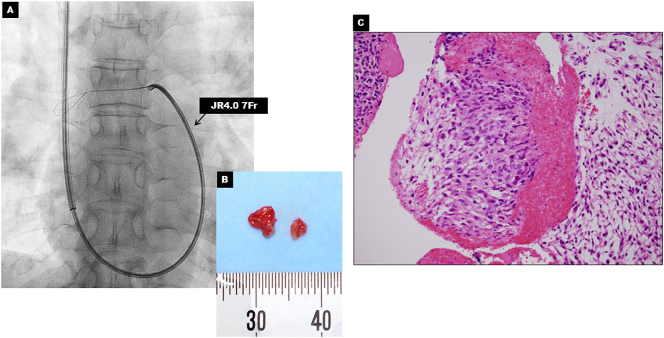

Pathological examination by biopsy was required to obtain definitive diagnosis. We decided to perform a safe and minimally invasive transcatheter aspiration biopsy [4]. Assisted by a pulmonary arteriograph, aspiration biopsy was performed using a 7Fr JR4.0 (Fig. 3A). Tissue samples were successfully obtained without complication (Fig. 3B) and PAIS was proved by pathological examination (Fig. 3C).

Fig. 3.

Transcatheter aspiration biopsy and pathological findings. (A) Fluoroscopy image showing transcatheter aspiration biopsy using the 7F JR4.0. (B) Gross appearance of tissue sample. (C) Biopsy specimen shows spindle cell sarcoma with prominent nuclear atypia that are consistent with pulmonary artery intimal sarcoma (hematoxylin-eosin staining x400).